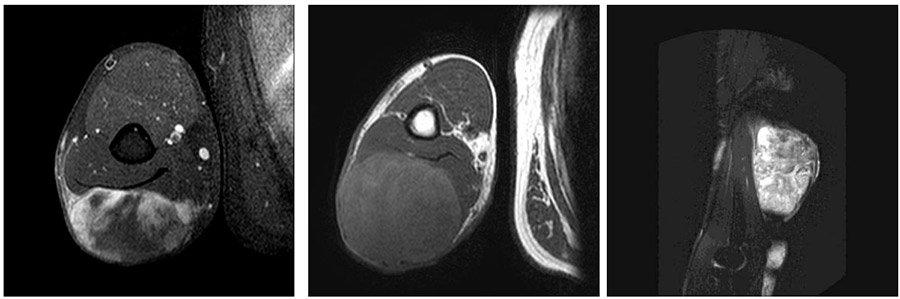

Ameliyat Öncesi: MR’da kol arka kısımda sınırları düzensiz heterojen yumuşak doku kitlesi görülmekte